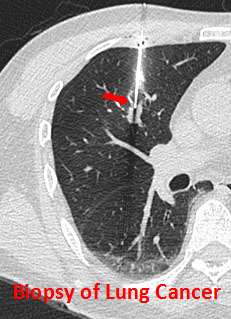

Lung Cancer & NSCLC Diagnosis

In addition to a physical examination, laboratory tests and imaging studies are needed. These tests include:

- Biopsy of the lung